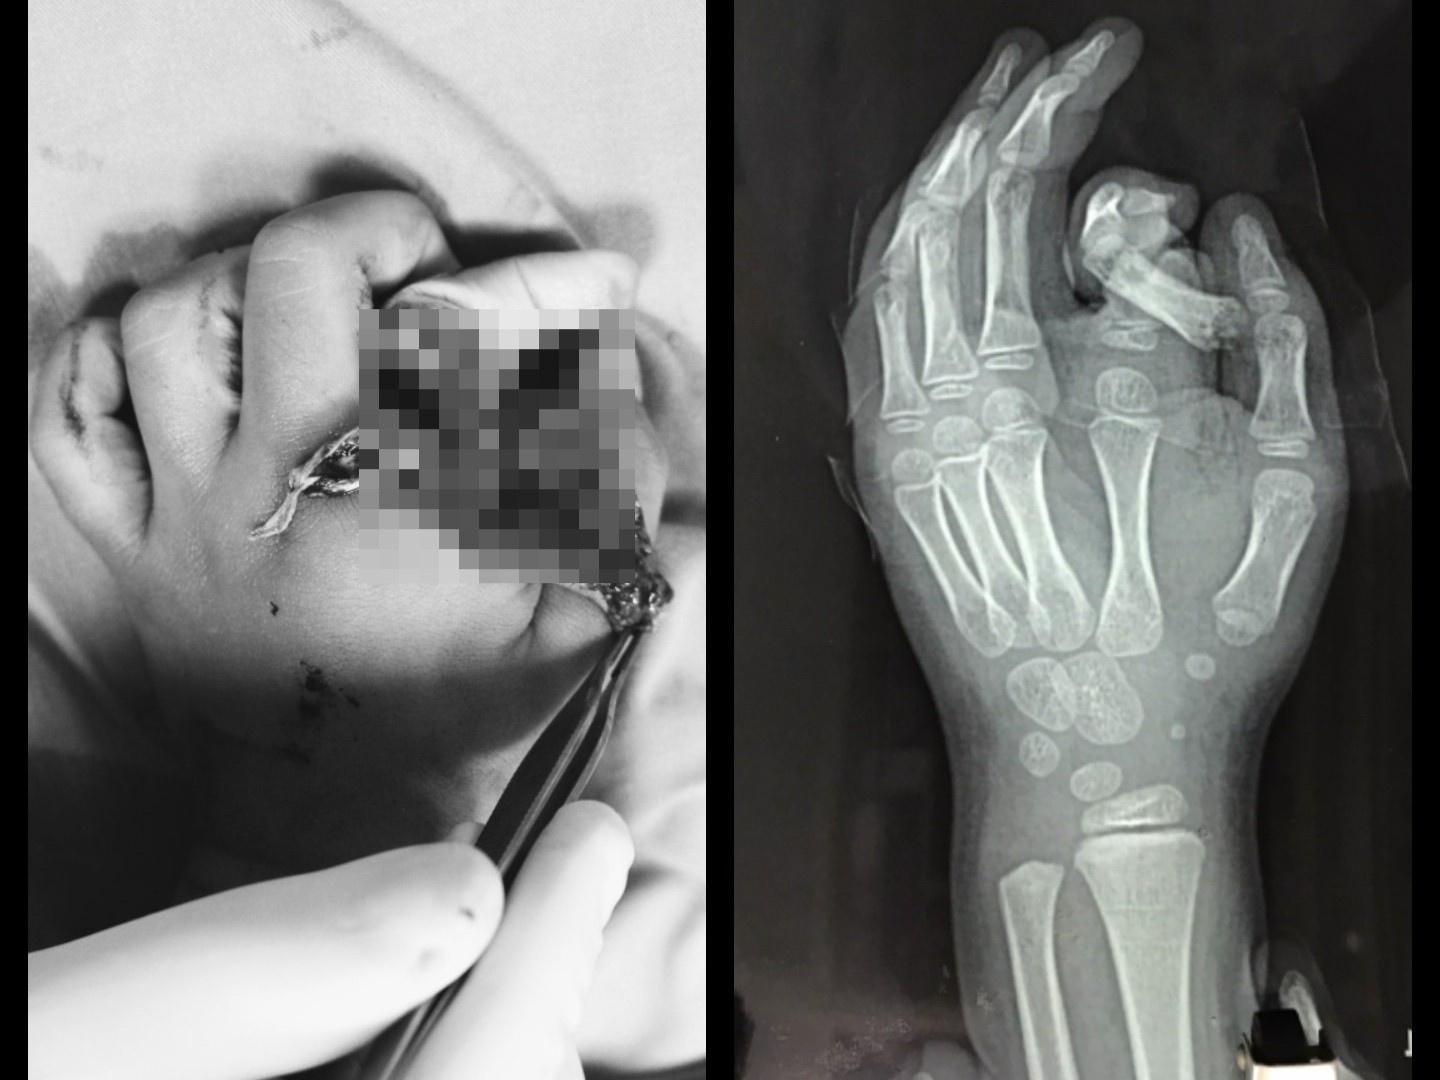

Bé trai nhập viện trong tình trạng ngón trỏ đứt rời, xoắn vặn, hệ thống thần kinh dây chằng bị nhổ bật một đoạn dài.

Mới đây, khoa Phẫu thuật tạo hình và Thẩm mỹ, Bệnh viện Đa khoa Xanh Pôn (Hà Nội), điều trị cho bé trai N.T.N., 6 tuổi, ở Hà Nội, bị thương nặng, ngón trỏ đứt rời.

Khi trẻ nhập viện, các bác sĩ đã cố gắng để bảo tồn và nối ngón tay. Tuy nhiên, do tình trạng dập nát quá nặng và bệnh nhân còn nhỏ tuổi nên hiện chưa thể nối được.

Ngón tay của bé trai bị đứt lìa, dập nát sau tai nạn. Ảnh: BVCC.